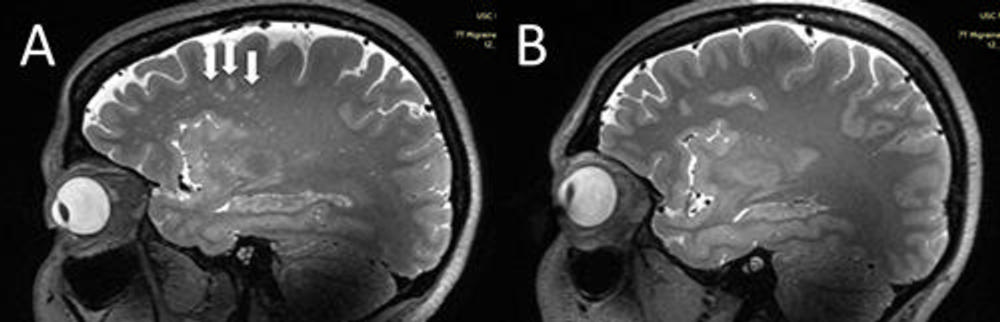

Figure 2. (A) Punctate deep white matter hyperintensities (WMH) (arrows) on sagittal T2-weighted MRI, more prominent in the frontal lobes. (B) Migraine-free control without punctate WMH.